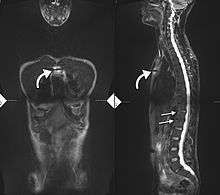

34-year old male with AS. Inflammatory lesions of the anterior chest wall are shown (curved arrows). Inflammatory changes are seen in the lower thoracic spine and L1 (arrows).

There is no direct test to diagnose AS. The Schober's test is a useful clinical measure of flexion of the lumbar spine performed during the physical examination.[11] Magnetic resonance imaging (MRI), and X-ray studies of the spine, which show characteristic spinal changes and inflammation of the sacroiliac joint, combined with a genetic marker blood test are the major diagnostic tools.